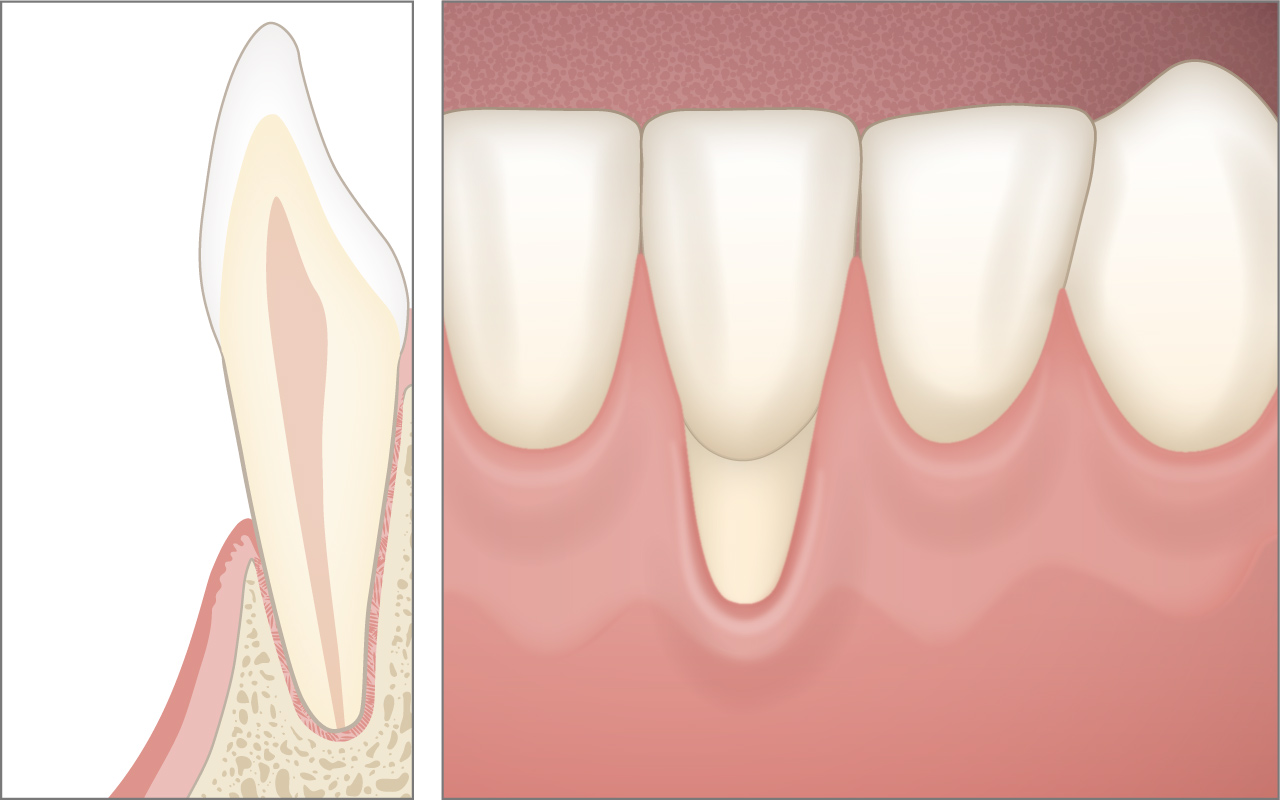

Was ist eine Zahnfleischrezession?

Eine Zahnfleischrezession ist der Rückgang des Zahnfleisches mit einer sichtbaren Entblössung der Zahnwurzel. Mehr als 50 Prozent der Bevölkerung zeigen einen oder mehrere Zähne mit einer Zahnfleischrezession.

Mehr ...Was ist eine Zahnfleischrezession und wie häufig kommt sie vor?

Eine Zahnfleischrezession ist der Rückgang des Zahnfleisches mit einer sichtbaren Entblössung der Zahnwurzel. Mehr als 50 Prozent der Bevölkerung zeigen einen oder mehrere Zähne mit einer Zahnfleischrezession.